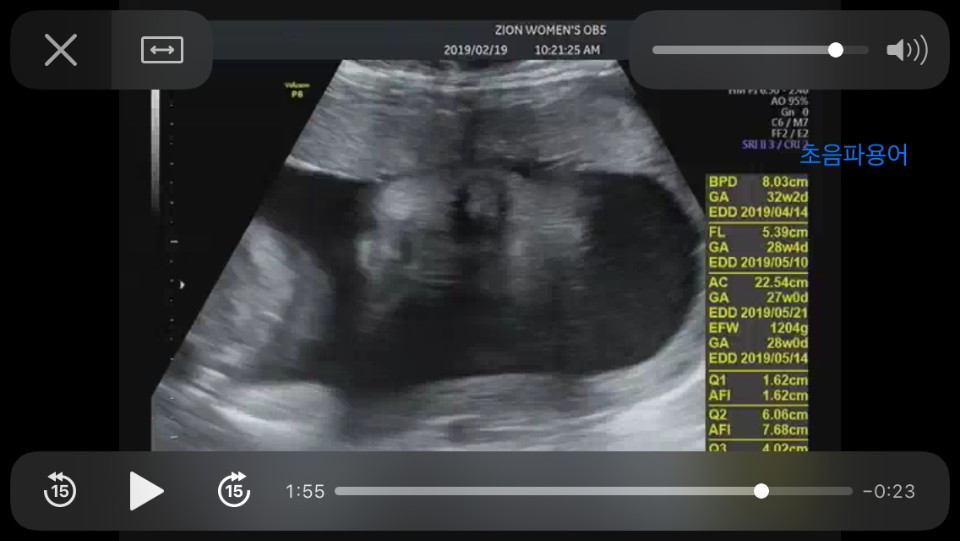

임신한 이후로 식성이 바뀌어서인지 카레가 그렇게 먹고싶었다. 카레 관련한 레시피를 찾고 가게들을 엄청 돌아다녔다. 이제 아기낳으면 갈수 없다고 생각이 들어 서울에 자주 가서 혼자 카레를 먹었다. 그덕인지 아이는 초음파 사진에서 인도 청년같은 곱슬머리를 하고 있었고, 태어나면 '엄마 여기가 어디에요? 인도에요?'라고 물어볼것만 같았다. 막상 태어난 아이는 그렇게까지 곱슬이 아니었지만 나를닮아 조금은 곱슬기가 있었는데 몇개월 지난 지금은 배냇머리가 다 빠지고 가느다란 예쁜 머리가 났다.